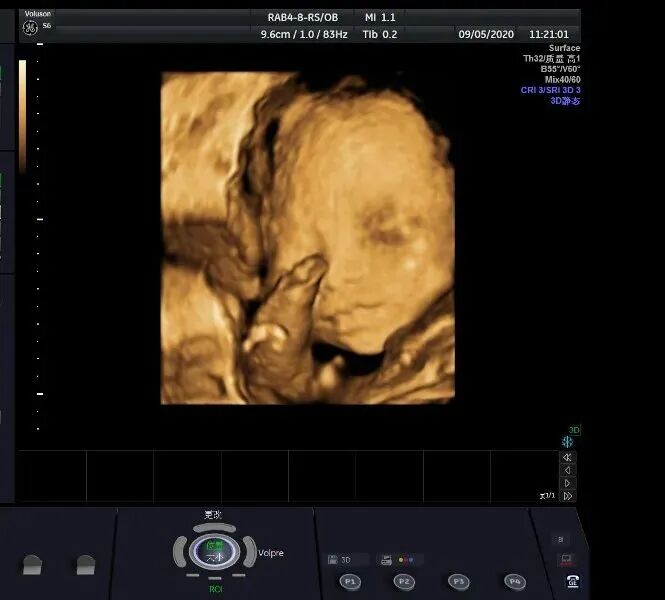

孕妈咪们都知道

孕中期有项不可缺少的排畸

四维彩超检查

不仅能立体显示胎儿器官发育情况

甚至观察到胎儿在母体里的状态

四维彩超还能通过实时立体成像

看到胎儿的形态及面部表情

还有宝宝在子宫内的一举一动